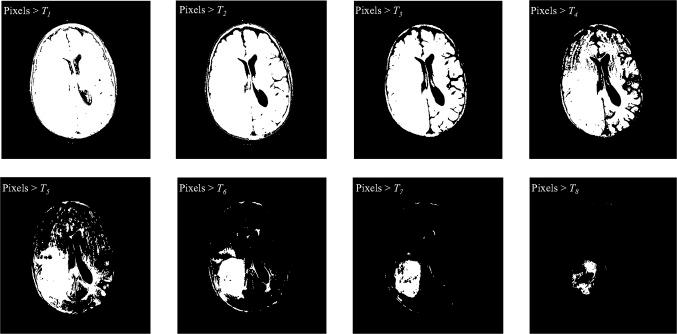

To isolate the brain from non-brain tissues using a fully automatic method may be affected by the presence of radio frequency non-homogeneity of MR images (MRI), regional anatomy, MR sequences, and the subjects of the study. In order to automate the brain tumor (Glioblastoma) detection, we proposed a novel approach of skull stripping for axial slices derived from MRI. Then, the brain tumor was detected using multi-level threshold segmentation based on histogram analysis. Skull-stripping method, was applied by adaptive morphological operations approach. This is considered an empirical threshold by calculation of the area of brain tissue, iteratively. It was employed on the registration of non-contrast T1-weighted (T1-WI) and its corresponding fluid attenuated inversion recovery sequence. Then, we used multi-thresholding segmentation (MTS) method which is proposed by Otsu. We calculated the performance metrics based on the similarity coefficients for patients (n = 120) with tumor. The adaptive algorithm of skull stripping and MTS of segmented tumors were achieved efficient in preliminary results with 92 and 80 % of Dice similarity coefficient and 0.3 and 25.8 % of false negative rate, respectively. The adaptive skull stripping algorithm provides robust skull-stripping results, and the tumor area for medical diagnosis was determined by MTS.